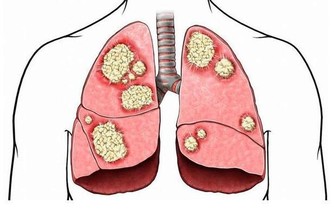

研究表明,體重過重或肥胖會增加罹患多種疾病的風險,如心臟病、高血壓、糖尿病等,這些疾病會縮短人的壽命。